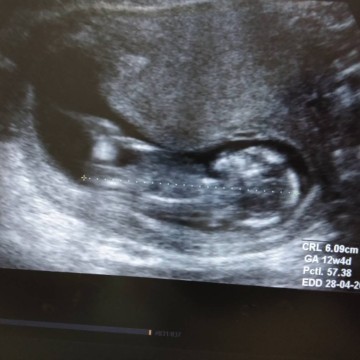

รูปซาว ตอน 12 w ตอนนี้ ท้องได้14w อยากถามแม่ๆว่ารู้เพศน้องตอนกี่วีค ค่ะ ขอบคุณค่ะ